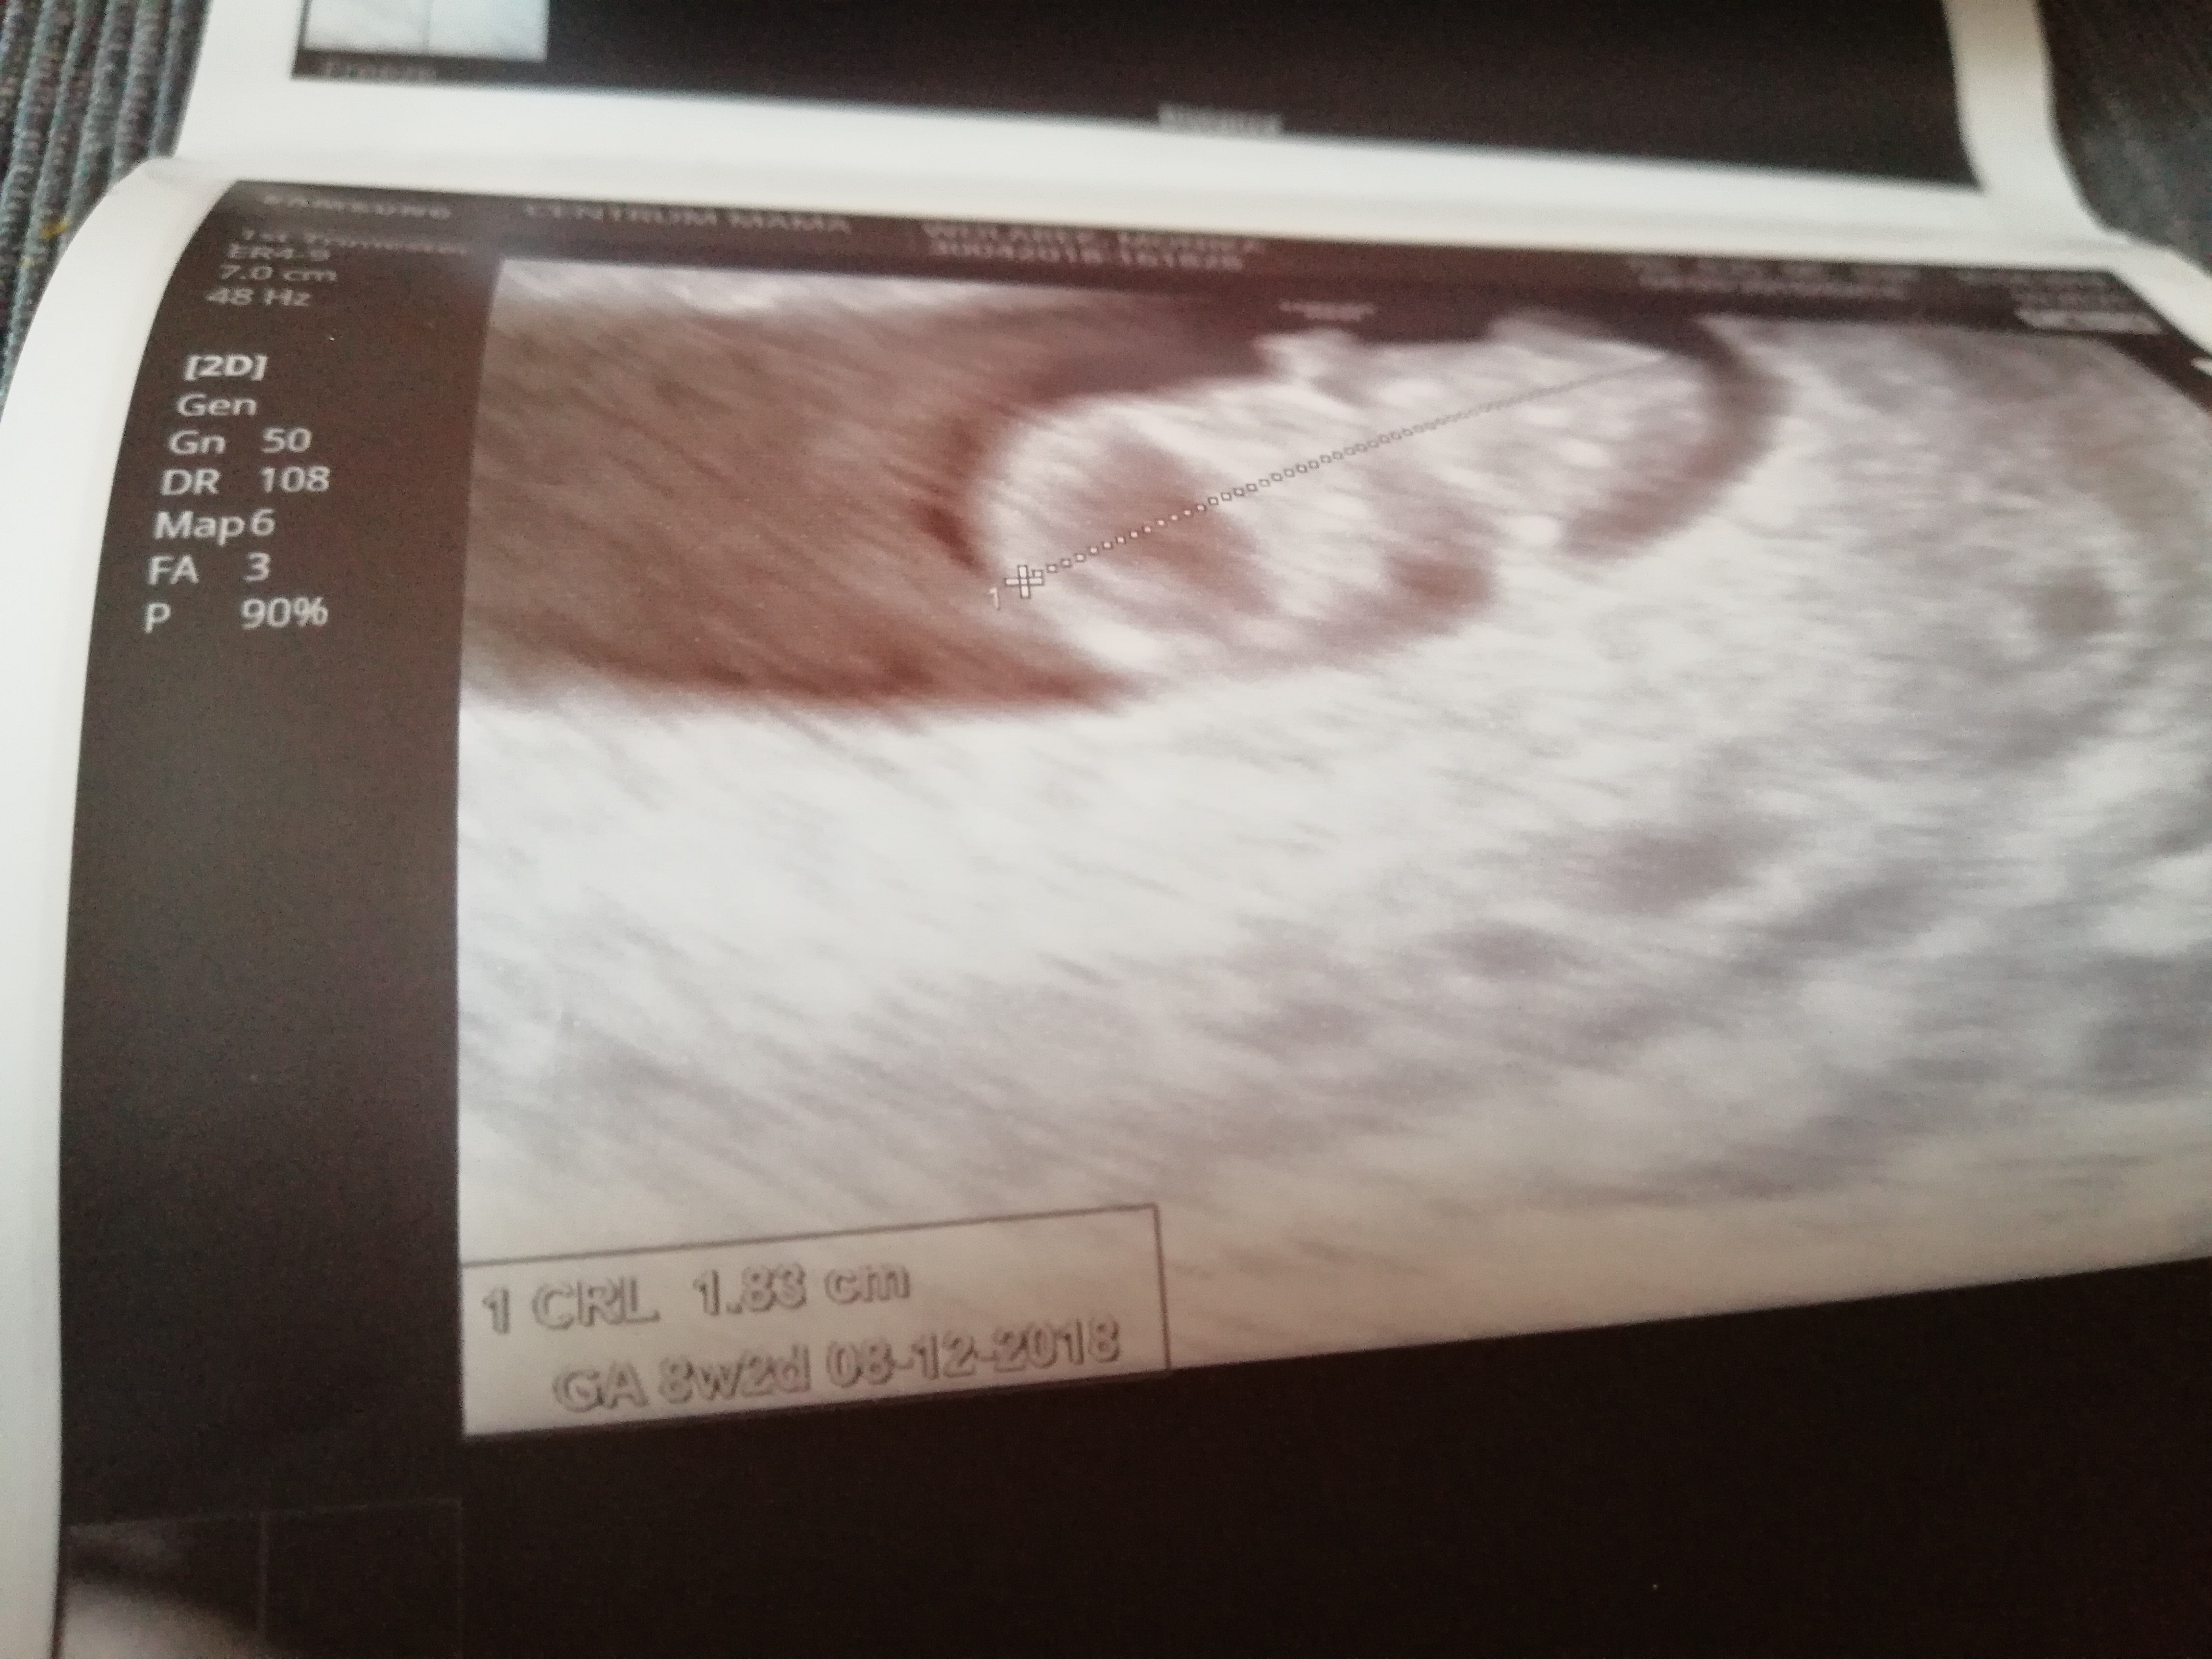

. Ostatnia miesiączka 4 marca

Nie wiem . Nie wiem czy dobrze patrze i odczytuje zdjecie@Słonik1982 hej bardzo dobrze ja biore luteine odkad sie dowiedzialam o ciazy. A ile dzidzia ma mm? Kiedy mialas om?